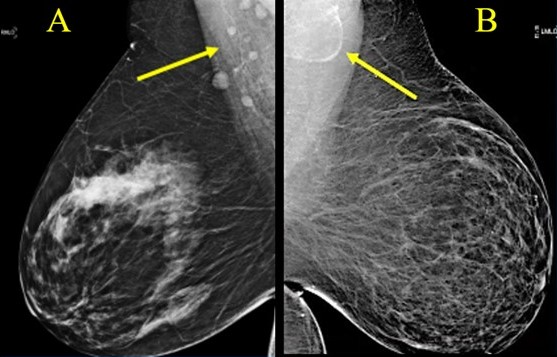

Variable LN morphology on screening mammograms in women with obesity due to ectopic fat deposition. A, Normal axillary lymph nodes measuring < 1.5 cm in 63-year-old woman with BM = 43.2. B, Fat-enlarged axillary node with large fatty hilum measuring 4.2 cm in 52-year-old woman with BMI = 45.8.

May 10, 2024 — According to the Summa Cum Laude Award-Winning Online Poster presented during the 124th ARRS Annual Meeting, fat-enlarged axillary nodes on screening mammograms can predict high cardiovascular disease (CVD) risk, Type 2 diabetes (T2DM), and hypertension (HTN).

Ultimately, among 1,216 women included in this ARRS Annual Meeting Summa Cum Laude Scientific Poster, 907 (74.6%) had a visible axillary LN on the index mammogram, and 232 (19.1%) women had fat-enlarged nodes—defined as larger than 20 mm in length due to an expanded fatty hilum. Women with fat-enlarged nodes had a high risk of CVD defined by PCE (OR = 2.6, 95% CI 1.5–4.2), as well as a higher prevalence of T2DM (OR = 4, 95% CI 2.1–7.7) and HTN (OR = 2.5, 95% CI 1.6–4.0). Fat-enlarged nodes were also associated with a trend toward higher risk of MACE (OR = 1.7, 95% CI 0.9–3.1) and LDL (OR = 1.4, 95% CI 0.9–2.1).